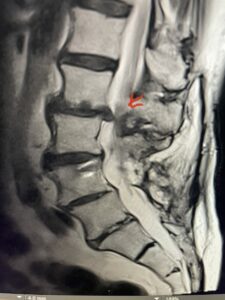

In patients who have lumbar spinal stenosis and significant cardio/pulmonary conditions, surgery is the last resort. However, some patients with these conditions may fail all means of conservative management where surgery becomes their only option for relief. In those patients, one should strive to do the least complex surgery that is necessary to get the job done for them. In this case study, we are confronted with a new problem in a 78 year-old male patient that was in poor medical condition who had had two prior lumbar laminectomies with resultant fusion and instrumentation from L4-S1. There was now retrolisthesis of L2-3 with severe stenosis (Fig.1)

Fig 1a: Sagittal T2 weighted lumbar MRI demonstrating severe L2-3 stenosis (red arrow)